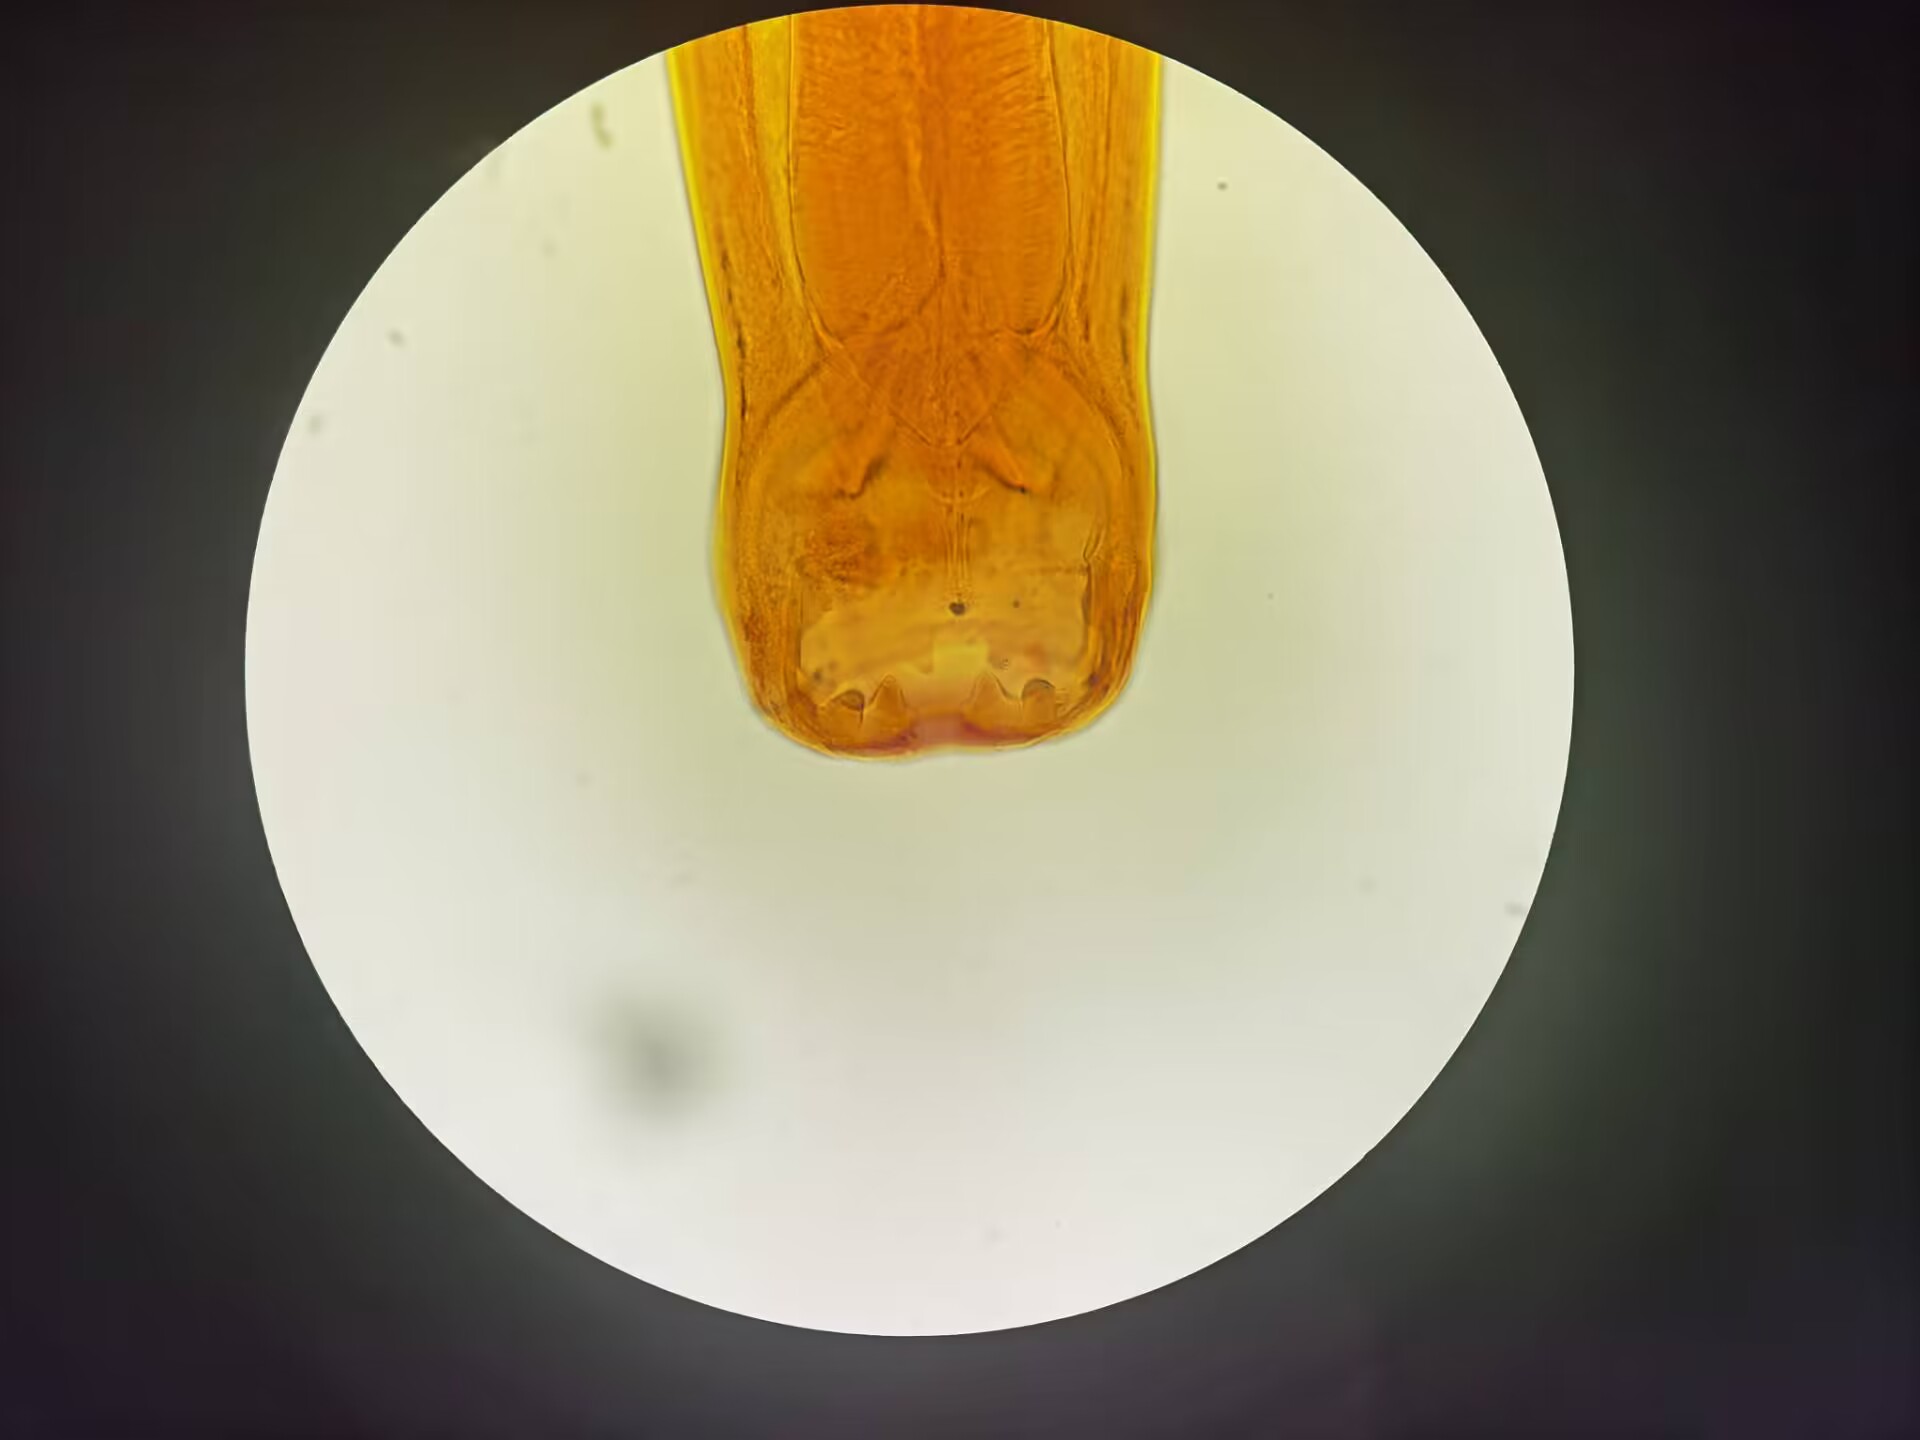

十二指肠钩虫口囊